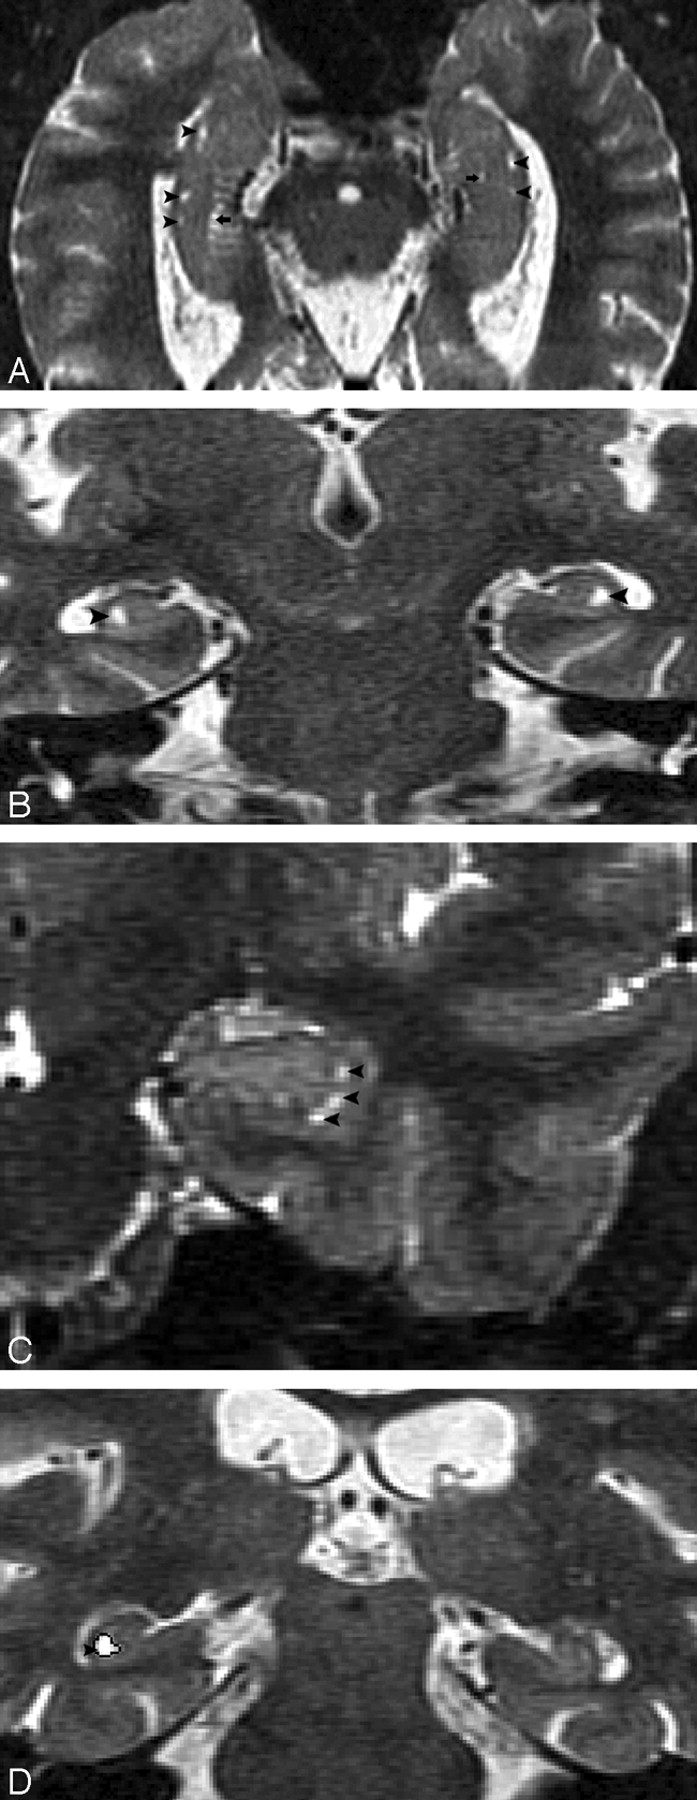

Hippocampal sulcus residual cavities (HSC) were identified on T2-weighted STIR coronal images by both location and CSF consistent signal intensity characteristics. HSC were typically located in the lateral portion of the hippocampus and within 5 mm of the margin of the temporal horn of the lateral ventricle (Fig 1A–D). HSC are isointense to CSF on both T1- and T2-weighted images. We measured the area of each cavity manually in every section by MIDAS software (New York University) (Fig 1D) and summed them across hemispheres to get each individual’s HSC score.

MR imaging appearance of hippocampal sulcus residual cavity (HSC).

A, The image was reformatted to a 1-mm-thick axial plane from the coronal T2 short-τ inversion recovery (STIR) scan, paralleling to the long axial of hippocampus (HSC, arrowheads; perihippocampal fissures [PHF], arrows).

B–D, Images were obtained by using the T2 STIR sequence (section thickness, 3 mm; HSC, arrowheads).

D, Region of interest of HSC (arrowhead).

On MR imaging, HSC appeared round, oval, or crescent, and the diameter ranges from 1 to 5 mm (Fig 1D). HSC were found with a prevalence of 64% in entire NC group and there was no significant difference between men and women (χ2(1) = 1.6; P > .05). The prevalence of HSC was 74% in AD compared with 75% in the age-matched NC group. In some cases, multiple cavities were present and appeared like a string of beads in both axial and coronal planes (Fig 1A, -C). In the NC subjects, 31% of the HSC were found in the hippocampal head, 50% were found in the hippocampal body, and 19% were found in the hippocampal tail. The observed prevalence of the HSC is found in Table 2.